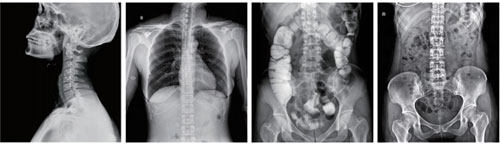

Meet the needs all parts of the human body, including Special positioning Radiography. It is suitable for fluoroscopy of various parts of the body (such as chest, abdominal, etc.) Partial angiography, such as esophagography, pyelography, salpingography. Obtain high-definition images and accurately capture lesions during fluoroscopy, avoiding missed diagnoses and misdiagnosis caused by blind shots.

Meet the needs all parts of the human body, including Special positioning Radiography.

It is suitable for fluoroscopy of various parts of the body (such as chest, abdominal, etc.)

Partial angiography, such as esophagography, pyelography, salpingography.

Obtain high-definition images and accurately capture lesions during fluoroscopy, avoiding missed diagnoses and misdiagnosis caused by blind shots.

● Orthopaedics

● Respiratory Unit

● Gastroenterology

● Gynecology

● Emergency Department

● Medical Examination

● Fever Clinic

● Traumatology

● Urology